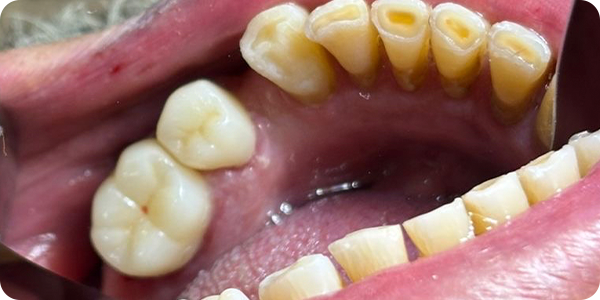

Material:

Zirconio multicapa AIDITE, valorado por su translucidez que mimetiza la estructura natural del diente y su equilibrio entre resistencia mecánica y transición de color natural.

Fresado:

Unidad XTCERA 500 plus. Su sistema de 5 ejes y precisión de 2 micras, se logró un detallado excepcional de los márgenes y la morfología oclusal.

Sinterizado y Acabado:

Tras el ciclo de cocción en un horno Cameo CSF-200L, las piezas pasaron por ajuste manual y un riguroso control de calidad, finalizando con un maquillaje personalizado para igualar el color.

La combinación de una planificación meticulosa, materiales de alta calidad como la zirconia AIDITE y el soporte educativo de nuevas tecnologías, permitió transformar una situación de desajuste en una rehabilitación funcional y estética. La cementación final demostró que la precisión digital puede compensar preparaciones clínicas subóptimas. La respuesta gingival tras las consultas de seguimiento fue positiva, logrando un sellado hermético.